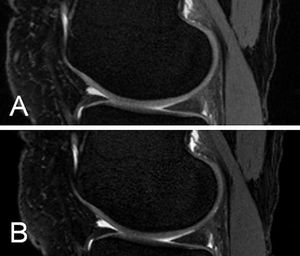

(A) 3D DESS with FA 25° and (B) 3D DESS with FA 90°. Cartilage-synovial fluid CNR is higher with 90° FA. Nevertheless, there are SAR issues with high FA. #MRI #3D_DESS #MRI_of_cartilage